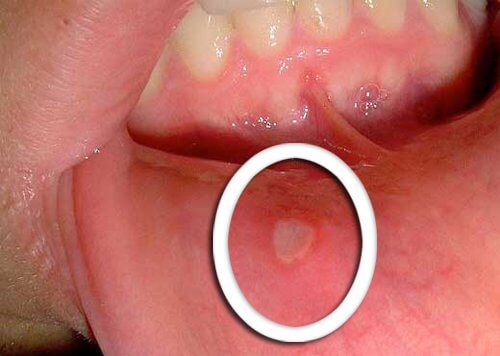

Fysiske ændringer i munden

- Det tidligste symptom på svælg kræft er små sår, der ikke heler.

- Det er typisk, at rødt eller hvidt vises på tungen, tandkødet eller på læberne.

- Vær opmærksom på eventuelle usædvanlige ændringer, der ikke forbedres på et par dage og gør opmærksom på dem overfor din læge.